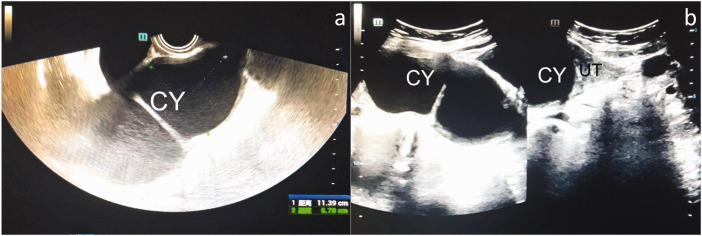

Accessory cavitated uterine malformation is a rare congenital anomaly of Müllerian duct development that typically affects younger women of reproductive age. The most common symptoms include chronic cyclic pelvic pain and severe dysmenorrhea, although diagnosis is frequently delayed owing to its rarity, multiple differential diagnoses, and low patient awareness. This report describes the case of a perimenopausal woman with accessory cavitated uterine malformation. The patient exhibited a palpable mass in the right lower abdomen without notable chronic pelvic pain or dysmenorrhea. It was initially misdiagnosed as an adnexal cyst in the right region based on ultrasound imaging, and laparoscopic exploration revealed a mass in the uterine corpus, leading to a revised diagnosis of accessory cavitated uterine malformation, which was confirmed through intraoperative findings and histopathological examination. The postoperative outcomes were favorable. This case underscores the diagnostic challenges of accessory cavitated uterine malformation, given the limited research on its pathogenesis and the absence of distinctive diagnostic markers. Imaging and histopathology are essential for an accurate diagnosis. Surgical intervention, especially laparoscopy, remains the preferred treatment, with excision typically resulting in a favorable postoperative prognosis.